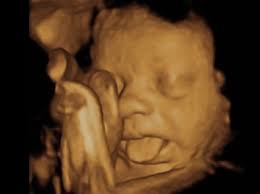

USG 4D: 5 Alasan Kenapa Kamu Harus Mengabadikan Momen Bersama Si Kecil!

Menanti kehadiran buah hati adalah salah satu momen paling membahagiakan dalam hidup. Setiap calon orang tua pasti ingin melihat tumbuh kembang si kecil, bahkan sejak ia masih berada dalam kandungan. Seiring berkembangnya teknologi, keinginan ini bukan lagi sekadar impian. Berkat teknologi pencitraan mutakhir, kini ada USG 4D yang memungkinkan Anda menyaksikan setiap gerak-gerik si kecil … Read more